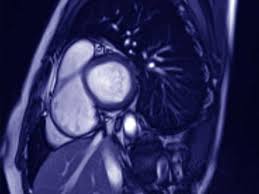

Mrt Klart Akuten Brustschmerz

Mrt Klart Akuten Brustschmerz from www.aerztezeitung.de